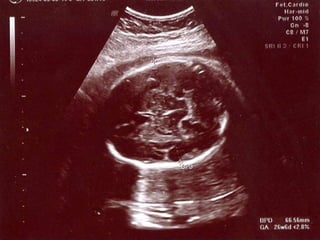

 USG ile fetal ölçümler tanıda kullanılır

 En yaygın tanım EFW %10 altında olmasıdır

 İUGG tanısıda 3 önemli kriter

1. Doğru GA

2. Fetal ağırlık tahmini

3. Gestasyonel yaş ve ağırlığa göre persentil

 HC, BPD, AC,FL kullanılır

 Hadlock gebelik yaşı için en sık kullanılır

HC,AC,FL

 10 günlük yanılma ile

Fetal Ağırlık Tahmini

 Ağırlık tahmininde 3 parametre bakmak

uygundur

 BPD, AC, FL en uygun bulunmuştur

(Hadlock)

 BPD dolikosefalde ölçmek hatalı olabilir

 FL en kolay ölçülür

 AC en önemli parametre